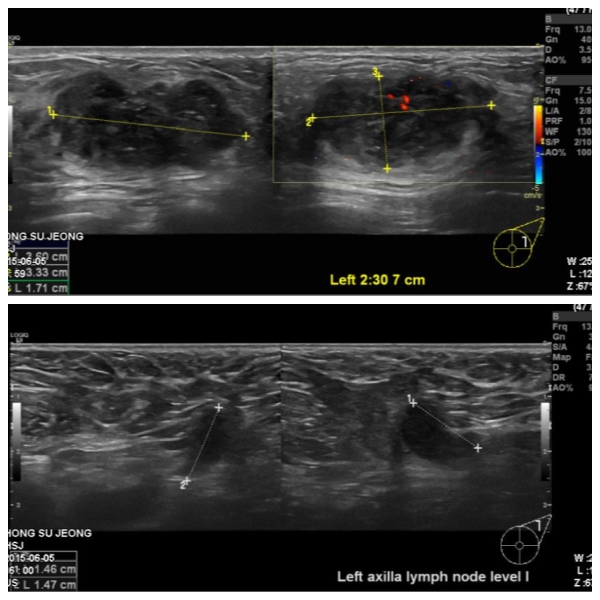

건강 검진상 이상 소견으로 내원하신 40대 여성 분으로 본원에서 좌측 유방 2시 30분에

유륜에서 7cm 떨어진 거리의 혹 조직검사와, 좌측 겨드랑이 림프절 세침검사 시행하여

좌측 침윤성 유관암과, 겨드랑이 전이로 진단 되었습니다.